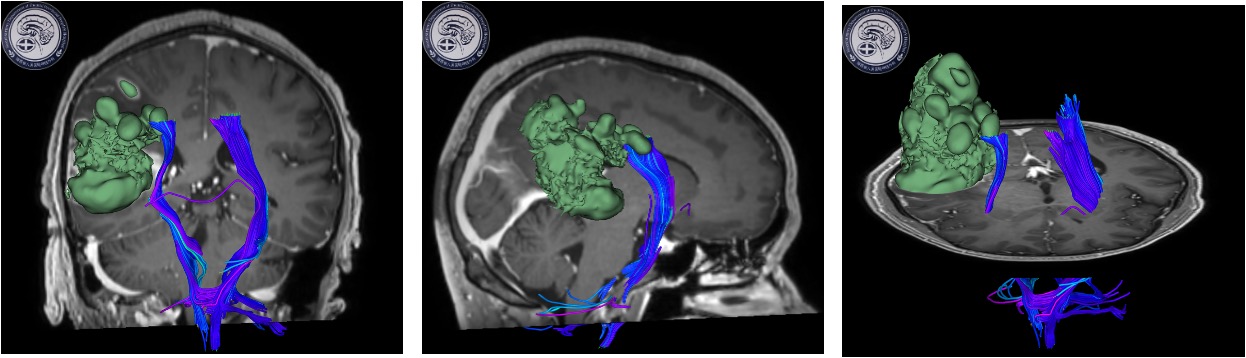

检查发现右颞顶叶多发占位病变,考虑胶质瘤。因肿瘤功能区关系密切,术后可能出现肢体运动障碍。如何做到在尽量全切肿瘤同时做好神经功能保护,对于神经外科医生来说是一种挑战。术前全科详细讨论病例制定了手术方案,决定在电生理监测下进行手术,近日由缪星宇主任医师、孟发财副主任医师、刘凯飞主治医师成功为患者实施了手术。术中在电生理运动诱发电位的监测下,结合多模态影像技术,显微镜下全切肿瘤,成功利用电生理监测技术保留运动区结构和功能,术后患者恢复顺利,病理结果确定胶质瘤诊断。

神经电生理监测是神经外科手术中监测神经功能完整性、减少神经损伤、提高手术质量所必不可少的组成部分,也是神经外科手术功能区保护的金标准。该患者采用的术中运动诱发电位监测是神经电生理监测技术之一,通过经电刺激神经或皮层,对照操作前的肌肉复合动作电位波幅和潜伏期基线,可判断神经、传导束的功能变化情况,为手术中实时监测神经功能提供有用的信息,是神经外科手术中常有监测技术之一,广泛用于颅脑和脊髓手术。在诱发电位的监测下,可以早期判断神经的位置和走形,监测神经功能变化,避免神经损伤。

通俗点说,术中神经电生理监测就像安装了GPS,哪里有神经信号传导要避开,哪里可以放心大胆的剥离,只要看到屏幕上跳动的信号,就一目了然。有了这样精准的导航,不仅能够彻底切除肿瘤,还最大程度保护了脑组织和功能。